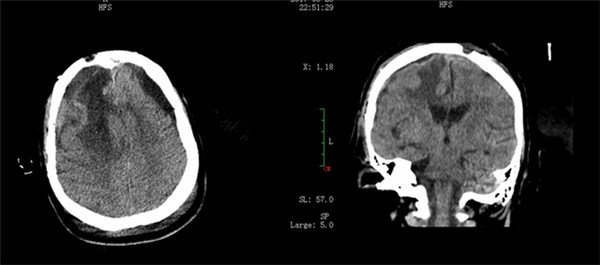

术前影像

术后影像